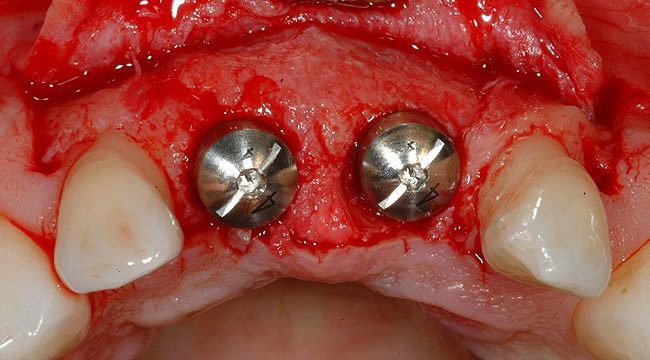

Figure 2  The orientation of the healing abutments after the patient had undergone extraction, guided bone regeneration, and implant placement. Note the wide spacing between the central incisor implants.

Figure 2

Figure 16   After extraction and 3 months of healing, two implants were placed in ideal position and with primary stability at sites Nos. 8 and 9. Implants were stable. Dehiscence defects exposing 13 threads were produced.

Figure 16